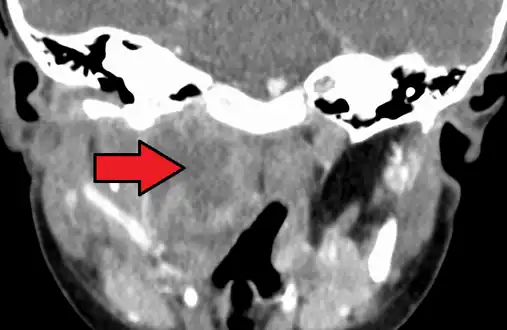

Large retropharyngeal abscess as seen on CT

Large retropharyngeal abscess as seen on CT Large retropharyngeal abscess as seen on CT

Large retropharyngeal abscess as seen on CT

A computed tomography (CT) scan is the definitive diagnostic imaging test.[4]